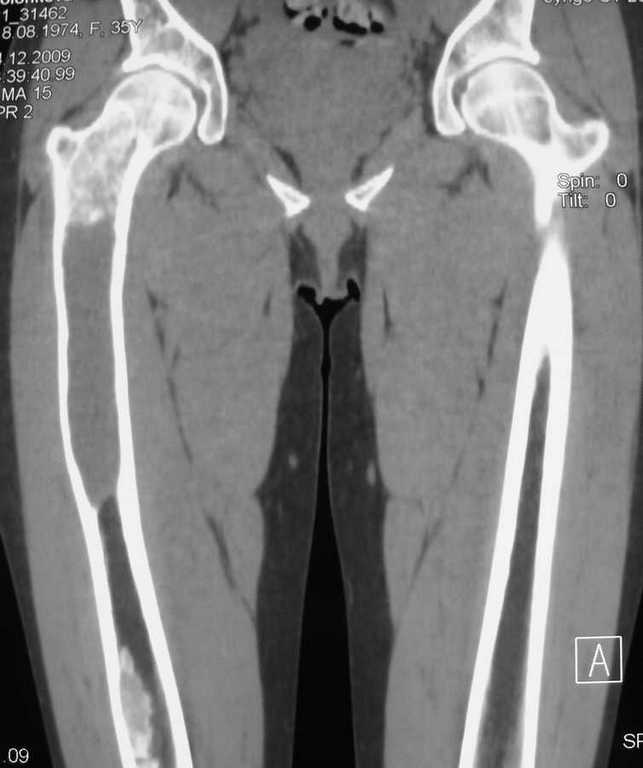

Большое спасибо всем, откликнувшимся на сообщение от 17 ноября

"Фиброзная дисплазия". В настоящее время пациентке выполнена

компьютерная томография и открытая биопсия правой бедренной кости с

последующим иммуно-гистохимическим исследованием.

Подтверждается диагноз фиброзной дисплазии без малигнизации.

Хотелось бы услышать мнение коллег относительно тактики дальнейшего

лечения пациентки, в первую очередь, варианты замещения дефекта в

случае резекции патологического очага с учётом обширности поражения.